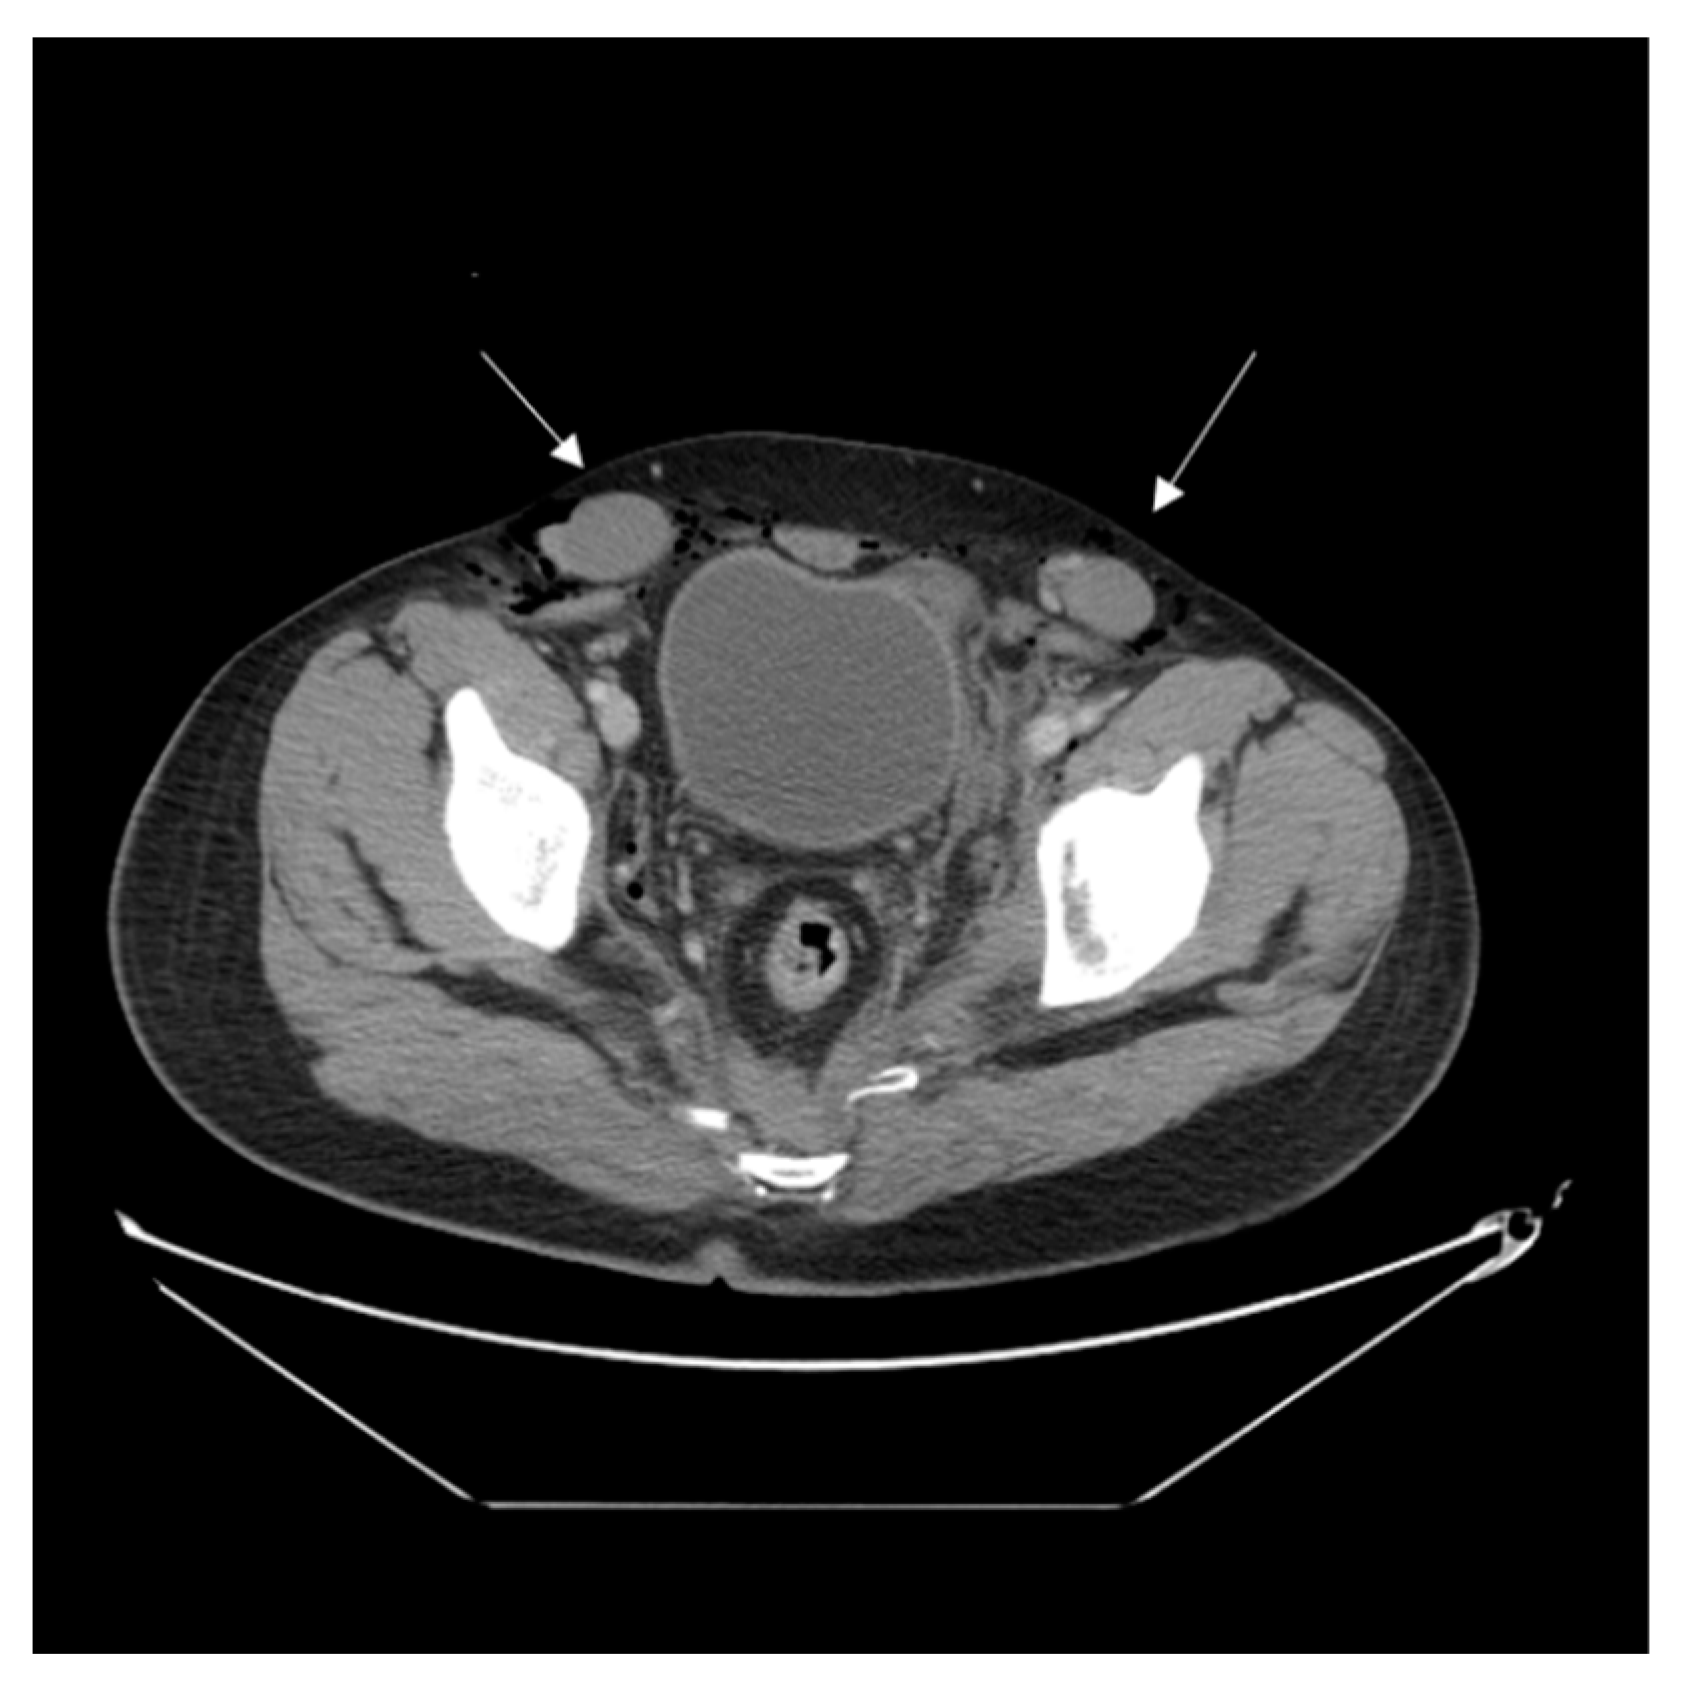

2. Case Report